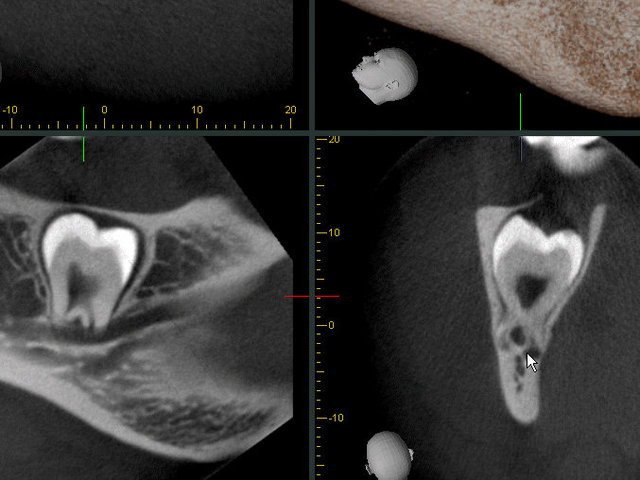

3D Röntgenbild

Sichtbarer Nerv im Zahnfach

Gekrümmte Wurzeln beim Nervenkanal